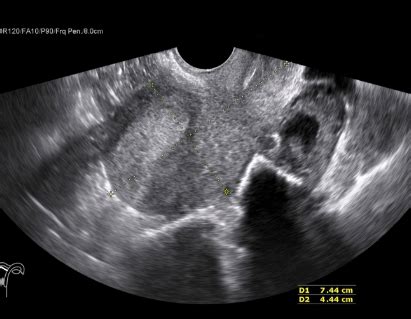

Ultrasound CM: Understanding Your Scan Results\n\nHey guys, ever had an ultrasound scan and found yourself staring at the report, wondering what all those numbers and letters mean? Especially that little ‘cm’ that pops up everywhere? Trust me, you’re not alone! Today, we’re going to dive deep into understanding what ‘cm’ means on your ultrasound results , breaking it down so you can feel more confident and informed about your health. Ultrasound is an incredible diagnostic tool, using sound waves to create images of the inside of your body without any radiation. It’s super safe and incredibly versatile, used for everything from peeking at a developing baby to checking on your internal organs, blood vessels, and even muscles. But the real magic often lies in the measurements – and that’s where centimeters (cm) come in. These tiny figures on your report aren’t just random numbers; they’re vital pieces of information that help your doctors understand what’s going on inside you. Without precise measurements in ‘cm’ , it would be incredibly difficult to accurately track progress, identify potential issues, or even determine normal organ sizes. For instance, in prenatal care, these centimeter measurements are the primary way doctors confirm gestational age, monitor fetal growth, and ensure everything is developing as it should. Similarly, when checking on internal organs like your liver or kidneys, their size, expressed in centimeters , can be a crucial indicator of health or disease. Even when a doctor is evaluating a suspicious lump or cyst, its dimensions in cm are paramount for deciding the next steps, whether it’s monitoring, further investigation, or treatment. So, if you’ve ever felt a bit lost in the medical jargon, stick around! We’re going to demystify ‘cm’ in ultrasound reports , giving you the knowledge to better understand what your body is telling you. This isn’t just about learning definitions; it’s about empowering you to engage more effectively with your healthcare providers and actively participate in your health journey. We’ll cover everything from the basics of ultrasound measurements to how centimeters are used in different types of scans, and most importantly, what these measurements ultimately mean for your health and well-being . Get ready to become a pro at interpreting your ultrasound scan results !\n\n## The Basics: What is Ultrasound and Why Do We Measure Things?\n\nLet’s kick things off by understanding the awesome ultrasound technology itself. Imagine sound waves, but at frequencies too high for human ears to hear – that’s what an ultrasound machine uses! A small handheld device called a transducer is placed on your skin, often with a little gel to help it glide. This transducer sends out these high-frequency sound waves into your body. When these sound waves hit something dense, like an organ, bone, or even a baby, they bounce back as echoes. The transducer then picks up these echoes, and a computer processes them to create real-time images on a screen. Pretty cool, right? This entire process is non-invasive, pain-free, and doesn’t involve any ionizing radiation, making it super safe for repeated use, especially during pregnancy. But why do we bother with all these measurements ? Well, guys, measurements are the backbone of diagnostic imaging. Simply looking at an image can tell a lot, but putting a precise number to the size of a structure adds a whole new level of detail and accuracy. For example, if a doctor sees a small dark area, it could be a simple cyst, but knowing its exact size in centimeters helps determine if it’s within a normal range or if it warrants further investigation. It’s like building a house – you wouldn’t just eyeball the dimensions; you’d use a tape measure to ensure everything is exactly where it should be. Similarly, in medicine, centimeters act as our precise ‘tape measure’ for internal structures. These measurements allow healthcare professionals to track growth over time, identify abnormalities in size or shape, and even pinpoint the exact location of masses or fluids. They provide objective data that can be compared against established normal ranges, helping to differentiate between healthy variations and potential medical conditions. Without these precise centimeter measurements , much of the diagnostic power of ultrasound technology would be lost. They’re not just numbers; they are the quantifiable evidence that guides clinical decisions, ensuring you get the most accurate diagnosis and appropriate care.\n\n## Decoding ‘CM’ in Your Ultrasound Report: Centimeters Explained\n\nAlright, let’s get down to brass tacks and really decode ‘cm’ in your ultrasound report . At its core, ‘cm’ simply stands for centimeters , a standard unit of length in the metric system. It’s the same centimeter you used in school for measuring things with a ruler – just applied to the structures inside your body. When you see a measurement like ‘2.5 cm’ on your report, it means that the structure being measured is two and a half centimeters long, wide, or deep. Simple as that! But its simplicity belies its incredible importance in medical diagnosis and monitoring. The primary purpose of using centimeters in ultrasound measurements is to accurately quantify the size of various internal structures. This includes everything from the length of a bone, the diameter of an organ, the thickness of a muscle, or the dimensions of a cyst or tumor. These precise measurements in ‘cm’ are absolutely crucial for several reasons. First, they help establish a baseline. When you have a scan, these initial centimeter measurements provide a starting point. If you have follow-up scans, doctors can then compare the new measurements to the old ones to track growth , regression, or stability of a particular condition. For example, if you have an ovarian cyst, your doctor will monitor its size in centimeters over time to see if it’s growing, shrinking, or staying the same. Second, these centimeter measurements allow doctors to compare your findings against established normal ranges for different ages, genders, and conditions. An organ that is significantly larger or smaller than the average size in centimeters might indicate an underlying issue. For instance, an enlarged liver (hepatomegaly) or an abnormally small kidney could point to different health problems. Third, centimeters help in accurate anatomical description and localization. When a report states a mass is ‘3 cm x 2 cm x 1.5 cm’ and located ‘5 cm superior to the bladder,’ it gives a very clear, objective picture to any healthcare professional reviewing your case. It provides a universal language for describing findings, ensuring consistency and clarity across different doctors and clinics. These measurements are truly the bedrock of objective medical assessment, turning what could be vague observations into quantifiable, actionable data for your care team. So, when you see those little ‘cm’ notations, remember they are the key to unlocking a more precise understanding of your internal landscape.\n\n### ‘CM’ in Prenatal Ultrasounds: Monitoring Your Little One’s Journey\n\nFor all you expectant parents out there, ‘cm’ in prenatal ultrasounds is probably one of the most exciting and frequently encountered measurements . These scans are truly a window into your little one’s world, and centimeter measurements are the primary way we monitor their incredible journey from a tiny embryo to a bustling baby. Early on, one of the first measurements taken is the gestational sac size in ‘cm’ and then the crown-rump length (CRL) , also in centimeters . This CRL measurement , taken from the top of the baby’s head to their bottom, is incredibly accurate for dating the pregnancy during the first trimester. It helps establish a precise due date, which is crucial for managing your prenatal care. As your pregnancy progresses into the second and third trimesters, a whole suite of fetal growth measurements come into play, all expressed in centimeters . These include: Biparietal Diameter (BPD) , which is the measurement across the baby’s head; Head Circumference (HC) , the distance around the baby’s head; Abdominal Circumference (AC) , the distance around the baby’s belly; and Femur Length (FL) , the length of the thigh bone. Each of these measurements in ‘cm’ provides valuable data points that your doctor plots on growth charts. These charts help assess if your baby is growing at an appropriate rate, if they’re a healthy size for their gestational age , and if there are any signs of growth restriction or excessive growth. For instance, if the femur length is consistently shorter than expected for the gestational age, it might warrant further investigation. Similarly, variations in abdominal circumference could indicate issues with nutrient uptake. It’s important to remember that babies grow at different rates, and one single measurement isn’t usually cause for concern. It’s the overall pattern of these centimeter measurements over time that provides the most meaningful information about your baby’s fetal development . Doctors use these detailed measurements not only to track fetal growth but also to check for specific developmental milestones and identify potential anomalies early on, allowing for timely intervention if needed. So, when you see those ‘cm’ figures on your prenatal report, know that each one is a precious piece of information helping your medical team ensure your baby is thriving.\n\n### ‘CM’ in Abdominal and Pelvic Ultrasounds: What Organ Sizes Tell Us\n\nMoving beyond pregnancy, ‘cm’ measurements are equally vital when you’re getting an abdominal or pelvic ultrasound . These scans are often done to investigate symptoms like pain, bloating, or to check on the health of your internal organs. The size of your organs , expressed precisely in centimeters , can tell your doctor a whole lot about your overall health and help in the diagnosis of various conditions. For example, in an abdominal ultrasound , organs like the liver, kidneys, spleen, and gallbladder are routinely measured. The liver size in ‘cm’ is a key indicator. An enlarged liver , or hepatomegaly, might suggest conditions such as fatty liver disease, hepatitis, or even heart failure. Conversely, a shrunken liver could indicate advanced cirrhosis. Similarly, the kidney size in ‘cm’ is crucial. Kidneys that are too small might point to chronic kidney disease, while enlarged kidneys could be a sign of obstruction, infection, or polycystic kidney disease. Your spleen is also measured; an enlarged spleen (splenomegaly) can be associated with infections, blood disorders, or liver disease. When we shift to a pelvic ultrasound , especially for women, measurements in ‘cm’ are absolutely fundamental. The uterus size in ‘cm’ is checked for normalcy. An enlarged uterus could indicate fibroids, which are benign growths, or adenomyosis. Ovaries are also measured, and the size of any ovarian cysts in ‘cm’ is carefully noted. Most ovarian cysts are benign and disappear on their own, but their size and characteristics help determine if they need monitoring or further intervention. For men, a pelvic ultrasound might involve measurements of the prostate gland in ‘cm’ . An enlarged prostate (benign prostatic hyperplasia or BPH) is common with age and its dimensions help assess the severity. Even blood vessels are measured; the diameter of the aorta in ‘cm’ , for instance, is vital for screening for abdominal aortic aneurysms. These centimeter measurements are not just arbitrary numbers; they are powerful health indicators that guide your doctor in understanding your body’s condition, identifying potential problems, and planning the most effective course of action. They allow for objective comparison against established norms, providing a concrete basis for diagnosis and treatment decisions. So, next time you hear about your organ size in ‘cm’ , you’ll know exactly why those numbers are so important!\n\n### ‘CM’ and Masses or Growths: Tracking Changes and Concerns\n\nNow, let’s talk about a particularly important application of ‘cm’ in ultrasound : when doctors are evaluating masses , growths , or other suspicious findings. Whether it’s a simple cyst, a fibroid, or something more concerning like a tumor, the initial ultrasound measurements in ‘cm’ are absolutely critical. These measurements provide the baseline data that healthcare providers use to track changes over time, which is often the most important factor in determining the nature and significance of a finding. When a new mass is discovered, the radiologist will carefully measure its length, width, and depth, all in centimeters . This creates a precise three-dimensional understanding of the growth . For example, a report might state, ‘a 4.2 cm x 3.8 cm x 3.0 cm complex renal cyst.’ This detailed information helps the doctor understand the size and characteristics of the cyst. If a follow-up scan is recommended, comparing these initial centimeter measurements with subsequent ones is paramount. Is the mass growing rapidly? Is it shrinking? Is it stable? The answers to these questions, derived from precise measurements in ‘cm’ , often dictate the next steps in your care. A growth that is significantly increasing in size may require further investigation, such as a biopsy, or a more aggressive treatment plan. Conversely, a stable mass might just need continued monitoring, or if it shrinks, it could be a sign of benign resolution. This applies to a wide range of findings: fibroids in the uterus, thyroid nodules , lymph nodes , or any other abnormal growth detected. Even for structures like gallstones or kidney stones, their size in ‘cm’ is important for determining the best management strategy – smaller stones might pass on their own, while larger ones might require intervention. It’s truly incredible how these simple centimeter measurements can guide such complex medical decisions. They provide objective, quantifiable data that takes the guesswork out of monitoring and managing conditions, ensuring that your doctors have the most accurate information to make informed choices about your health . Always remember that while a measurement in ‘cm’ gives you the size , its significance always needs to be interpreted by your doctor in the context of your overall health history and other diagnostic findings.\n\n## What Do These Measurements Really Mean for You?\n\nSo, guys, we’ve talked a lot about what ‘cm’ in ultrasound stands for and how it’s used in different scenarios. But here’s the kicker: *what do these measurements really mean for you, the patient*? This is where the rubber meets the road. While knowing that a cyst is 3 cm or that your baby’s femur length is 5 cm is helpful, the true value comes from the interpretation of these numbers within your unique medical context . First and foremost, remember that these centimeter measurements are just one piece of the puzzle. Your doctor doesn’t just look at a number in isolation. They consider it alongside many other factors: your symptoms, your medical history, results from other tests (like blood work or other imaging scans), and their clinical expertise. For example, a 2 cm ovarian cyst might be completely normal for one person, but if another person has specific symptoms or a history that suggests otherwise, that same 2 cm cyst could be viewed differently. This is why the doctor’s role is absolutely crucial. They are the ones who put all these pieces together. They compare your measurements against established normal ranges, but also factor in individual variations. There’s often a spectrum of ‘normal,’ and what’s normal for one person might be slightly different for another. Don’t fall into the trap of self-diagnosing by just looking up ‘normal organ sizes in cm’ online. The internet can be a great resource, but it lacks the critical ability to provide personalized medical context and expert interpretation . Your doctor will explain if your measurements are within expected limits, if they indicate something requiring further attention, or if they need to be monitored. They will tell you if a specific centimeter measurement is a cause for concern or just a benign finding. The key takeaway here is empowerment through understanding, not panic. Knowing that your ultrasound report contains precise measurements in centimeters means you have objective data about your body. This allows you to ask more informed questions during your appointments, engage meaningfully in discussions about your health, and feel more confident about the care you’re receiving. Always ask your doctor to explain what your specific centimeter measurements mean for you and your health journey. That dialogue is gold, guys!\n\n## Pro Tips for Understanding Your Ultrasound Results\n\nAlright, you savvy health advocates! Now that you’re well-versed in what ‘cm’ means on your ultrasound reports , let’s wrap things up with some practical pro tips for understanding your ultrasound results . These tips will help you navigate your healthcare journey with more confidence and ensure you’re getting the most out of your medical appointments.\n\nFirst and foremost: Ask questions! Seriously, guys, this is your health, and you have every right to understand what’s happening. When your doctor explains your ultrasound results , if anything is unclear, don’t hesitate to ask for clarification. You can say things like, ‘Could you please explain what this 5 cm measurement means for my specific condition?’ or ‘Is this size in centimeters within the normal range, and if not, what are the implications?’ A good doctor will appreciate your engagement and take the time to explain things in a way you can understand. There are no stupid questions when it comes to your health!\n\nSecond: Get a copy of your report and images. Many clinics and hospitals now offer online portals where you can access your medical records and imaging reports. Having your own copy allows you to review the details, including all the centimeter measurements , at your own pace. This can be super helpful for remembering what was discussed and preparing for follow-up appointments. It also empowers you to keep a comprehensive record of your health, which is invaluable if you ever switch doctors or need a second opinion. Plus, you can reference this article to make sense of the ‘cm’ notations directly on your report!\n\nThird: Don’t Google everything, but do read reliable sources. I know, I know, it’s tempting to jump straight to Dr. Google after an appointment. While doing your own research is a great step towards empowerment , be mindful of where you get your information. Stick to reputable medical websites, academic institutions, and trusted health organizations. Avoid forums or anecdotal sites that can cause unnecessary anxiety. Use the information you gain (like from this article!) to formulate intelligent questions for your doctor, rather than self-diagnosing.\n\nFourth: Understand that context is key. We’ve stressed this throughout, but it bears repeating: a single measurement in centimeters is rarely meaningful on its own. It’s always interpreted within the broader context of your clinical picture. Try to focus on the overall message from your doctor, rather than fixating on one specific number.\n\nBy following these tips, you’ll not only understand your ultrasound results better but also become a more active and informed participant in your own healthcare, which is truly what empowerment is all about!\n\n## Conclusion\n\nPhew! We’ve covered a lot of ground today, guys, all about understanding ‘cm’ in your ultrasound reports . From the basics of how ultrasound technology works to the specific ways centimeter measurements are used in everything from prenatal care to assessing organ health and tracking growths , you’re now armed with some serious knowledge. We’ve seen that these seemingly small measurements are, in fact, incredibly powerful pieces of information that your healthcare providers use to make critical decisions about your health. They offer objective data for tracking progress, diagnosing conditions, and ensuring you receive the best possible care. The main takeaway? Don’t let medical jargon intimidate you. By knowing that ‘cm’ simply means centimeters and understanding its diverse applications, you can transform from a passive recipient of information into an informed patient who actively participates in their health journey. Remember to always engage with your doctors, ask questions about your specific measurements and their implications , and use reliable resources to deepen your understanding. Your health is your most valuable asset, and being informed is one of the best ways to protect it. Keep those questions coming, and stay empowered!